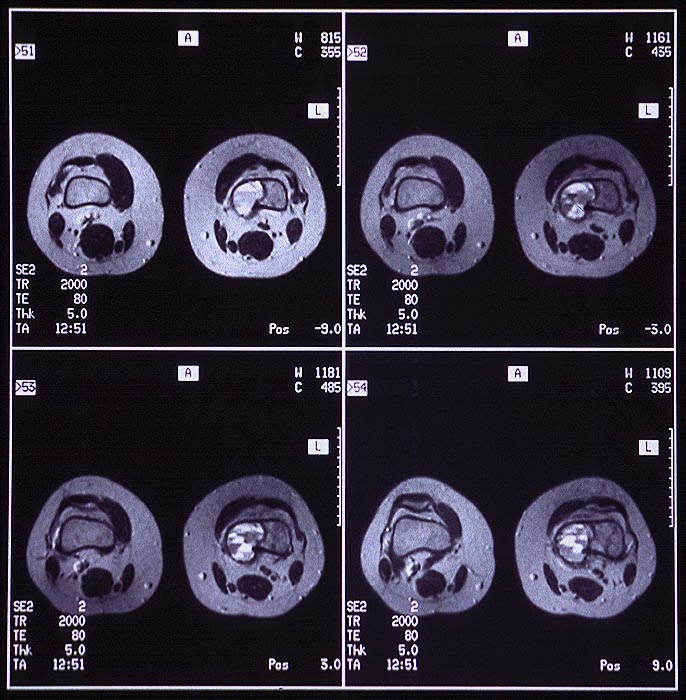

MRT: In der distalen linken Femurmetaphyse medial eine exzentrisch gelegene mehrkammrige Zyste. Im Kernspintomogramm erkennt man bei starker T2-Gewichtung Flüssigkeitsspiegel.